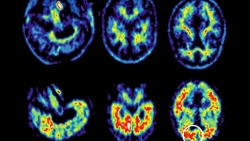

| Triệu chứng tâm thần như thờ ơ được cho là dấu hiệu đầu tiên của bệnh Alzheimer. (Nguồn: New Atlas) |

Trọng tâm nghiên cứu gần đây của bà Yao Ying Ma đã chuyển sang bệnh thoái hóa thần kinh. Các triệu chứng tâm thần tương tự như khi sử dụng chất kích thích (thay đổi tâm trạng, thờ ơ và lo lắng) hiện được coi là một số dấu hiệu sớm nhất của chứng sa sút trí tuệ.

CP-AMPAR cho phép canxi đi vào tế bào thần kinh. Trong các nghiên cứu trên động vật, các nhà nghiên cứu phát hiện việc quá tải canxi sẽ dẫn đến tổn thương tế bào thần kinh, chính điều này có khả năng gây ra sự thờ ơ và các vấn đề về vận động, báo hiệu giai đoạn sớm nhất của bệnh Alzheimer.